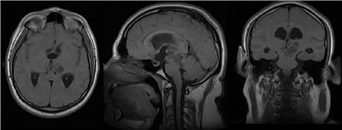

Imagen 1 Imagen heterogénea tabicada de componente hipointenso, con efecto volumétrico, de presencia en el interior localizada en el área pretectal, diencéfalo y periventricular.